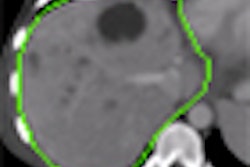

The researchers have further enhanced the software by adding color coding of different contrast enhancement patterns: yellow when the lesion remains more enhanced than the surrounding parenchyma, and green when it changes from hyper- to hypoechoic with regard to liver parenchyma.